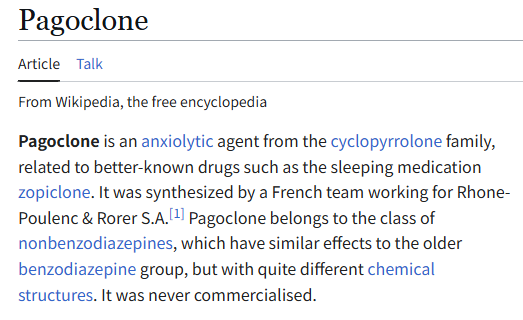

首先,从定义上讲,“反解离(anti-dissociative)”并不是一个标准的医学术语或者广泛认同的药理学分类。在正规资料,比如医学文献、维基百科、精神药理学教科书中,目前并没有“反解离药物”这个正式概念。

看上去像是为了描述某类特定效应而创造的术语(可能是nmda受体活性增强),用来对抗因NMDA受体拮抗剂(比如氯胺酮、DXM、PCP等)引发的解离体验(dissociation)。

那么更常见的是将其归入认知增强剂(cognitive enhancers),特别是改善认知连接性(connectivity)和现实感知(reality testing)的类型。